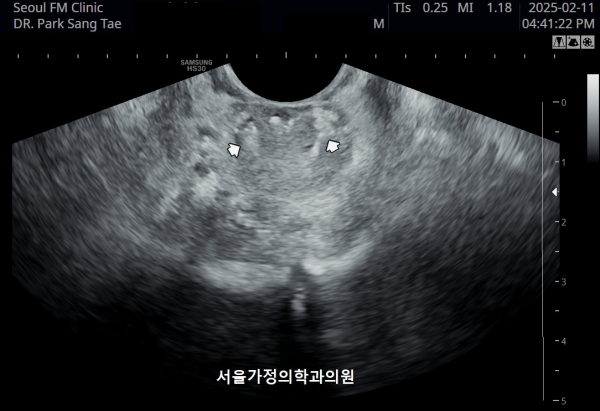

내원 당일 전립선의 정면 초음파 사진상 좌우 사정관 입구의 결석과 전립선의 이행구역에 비대해진 결절 그리고 우측 전립선 결절내 전립선 낭종이 관찰되며

방광쪽으로 커져 배뇨장애와 급박뇨가 심해 지고 있는 경직장 전립선 초음파 사진입니다.

This is a transrectal prostate ultrasound image taken on the day of the patient's first visit, showing stones at the openings of both ejaculatory ducts, an enlarged nodule in the transitional zone of the prostate, and a prostatic cyst within the right prostatic nodule. The prostate is enlarged toward the bladder, contributing to worsening voiding dysfunction and urgency.